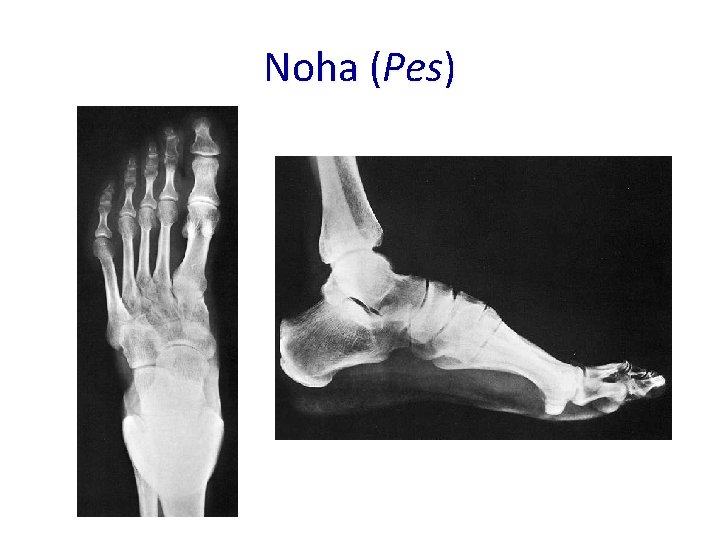

Noha (Pes)